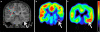

Dysembryoplastic neuroepithelial tumors (DNTs) are typically hypometabolic but can show increased amino acid uptake on positron emission tomography (PET). To better understand mechanisms of amino acid accumulation in epileptogenic DNTs, we combined quantitative α-[(11)C]methyl-L: -tryptophan (AMT) PET with tumor immunohistochemistry. Standardized uptake values (SUVs) of AMT and glucose were measured in 11 children with temporal lobe DNT. Additional quantification for AMT transport and metabolism was performed in 9 DNTs. Tumor specimens were immunostained for the L: -type amino acid transporter 1 (LAT1) and indoleamine 2,3-dioxygenase (IDO), a key enzyme of the immunomodulatory kynurenine pathway. All 11 tumors showed glucose hypometabolism, while mean AMT SUVs were higher than normal cortex in eight DNTs. Further quantification showed increased AMT transport in seven and high AMT metabolic rates in three DNTs. Two patients showing extratumoral cortical increases of AMT SUV had persistent seizures despite complete tumor resection. Resected DNTs showed moderate to strong LAT1 and mild to moderate IDO immunoreactivity, with the strongest expression in tumor vessels. These results indicate that accumulation of tryptophan in DNTs is driven by high amino acid transport, mediated by LAT1, which can provide the substrate for tumoral tryptophan metabolism through the kynurenine pathway, that can produce epileptogenic metabolites. Increased AMT uptake can extend to extratumoral cortex, and presence of such cortical regions may increase the likelihood of recurrent seizures following surgical excision of DNTs.